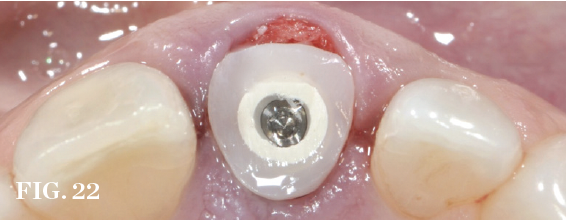

Guided Bone Regeneration

Management of the defect between the implant and socket walls and contour enhancement beyond the facial/buccal socket wall are almost always required in immediate placement approaches. Bone grafting of the residual horizontal defect and, at times, buccal contour augmentation are used to compensate for expected buccal plate changes resulting from extraction, especially when the bone morphotype is thin (Figure 19 through Figure 22). Soft-tissue grafts can be used to further support stable facial tissues, but they will not completely prevent changes in bone volume that are associated with postextraction remodeling (Figure 23 and Figure 24).

(21.) Guided bone regeneration using a collagen membrane and adapted bone graft.

Figure 21

(22.) Prefabricated custom healing abutment. Note the facial cutback to allow for the addition of a connective tissue graft to level the gingival margin with the contralateral dentition.

Figure 22